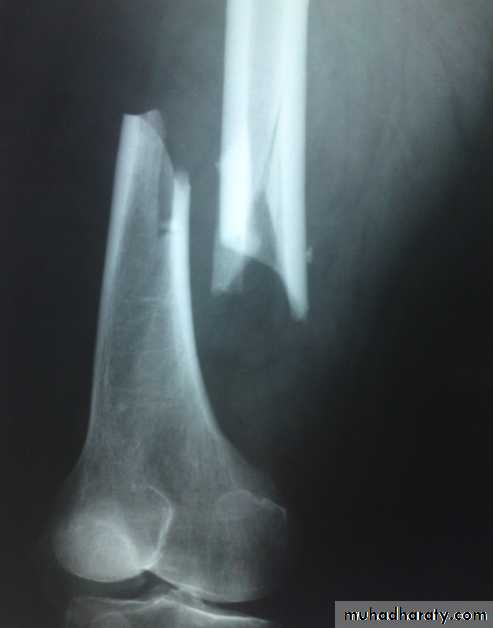

Supracondylar fractures of femur

In young adults after high energy injury.

In elderly osteoporotic after trivial injury.

Intercondylar extension may occur.

Supracondylar fracture with intercondylar extension

Supracondylar fracture femur